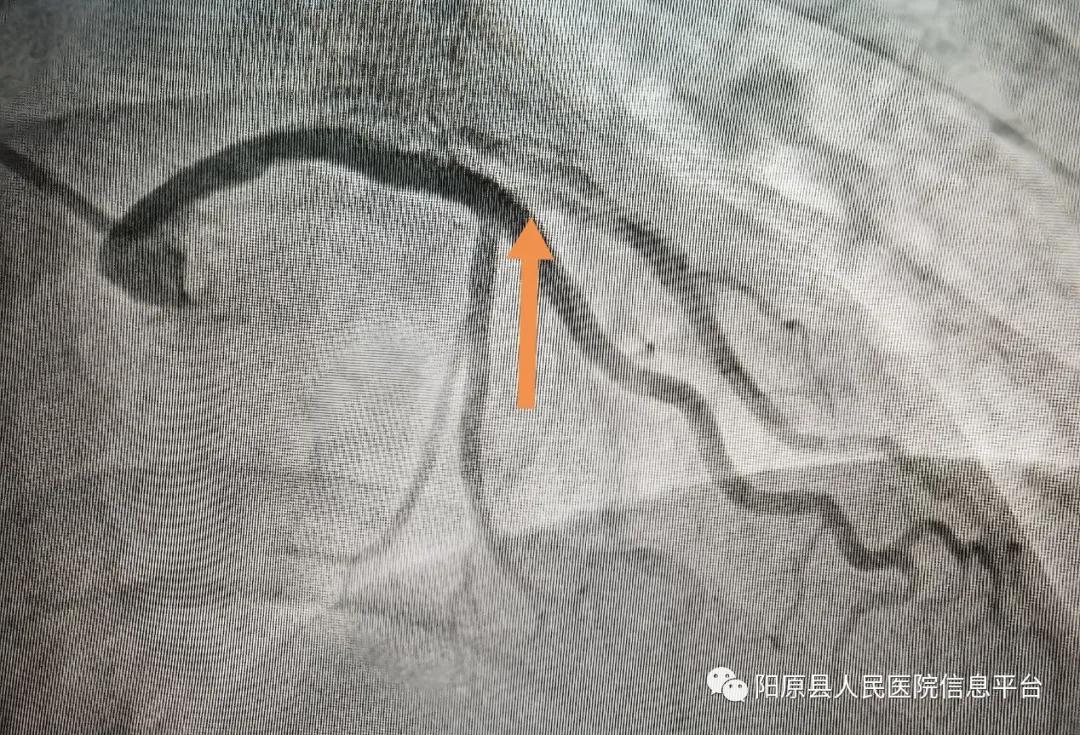

行冠脉造影示: